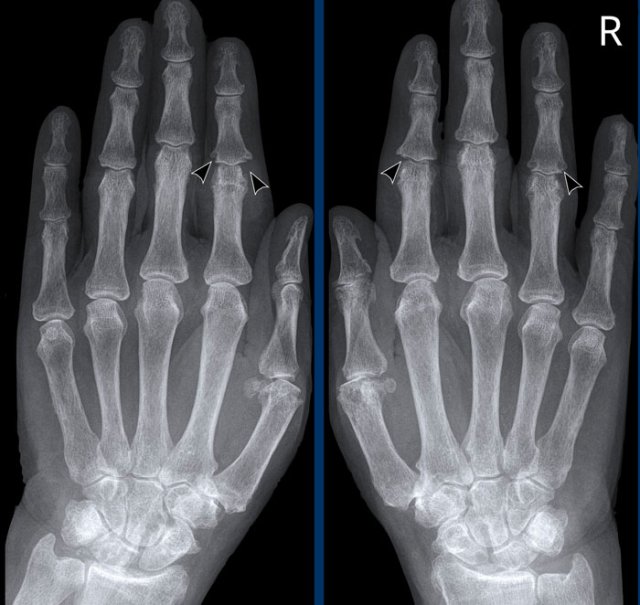

Rheumatoid arthritis in the feet Rheumatoid arthritis in the feet

In this case of rheumatoid arthritis there are marginal erosions adjacent to almost all MTP joints (arrowheads).

The 5th MTP joint is most frequently involved in  rheumatoid arthritis.

When erosions are as severe as in this case, it can look like pencil-in-cup deformity (white arrow) as is frequently seen in psoriatic arthritis.

However, the primarily affected MTP joints distribution and less affected interphalangeal joints is the clue that this is a case of rheumatoid arthritis.